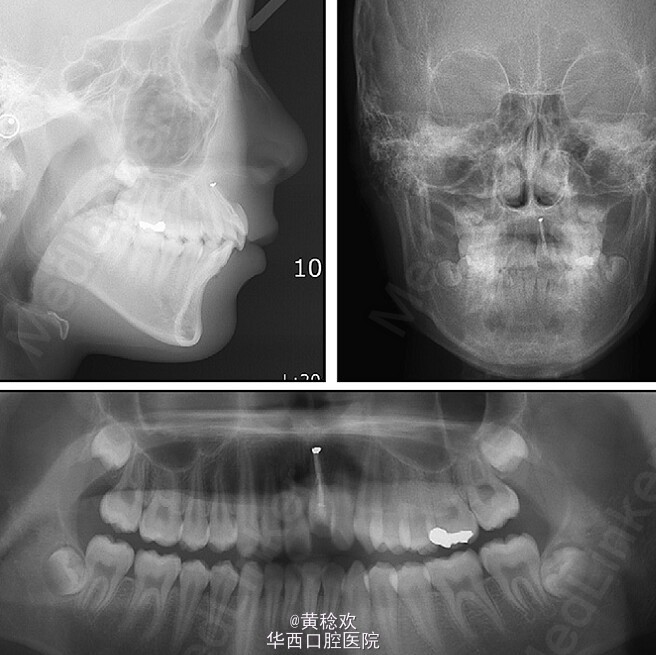

牙齿脱位对牙周膜、牙槽骨、牙龈、牙髓和牙骨质造成严重损害。脱位牙再植后经常伴有牙骨粘连等并发症。牙骨粘连指的是局部牙骨质和周围牙槽骨融合,多起因为牙齿正在萌出过程中或萌出后受到机械性、温度或者代谢产物刺激,对牙周膜造成损伤,好发于恒切牙。 牙骨粘连可通过临床和放射片检查诊断。临床检查包括低咬合状态、叩诊和松动度测试,最明显的特征是即便该牙施加正畸牵引力后也无法移动。整个牙的牙骨粘连可以通过放射片显示,其特征为无明显的牙周膜影响。但是如果该牙只有颊侧或者舌侧粘连,放射片上很难判断。近年来,CBCT的引入,可以逐渐将放射检查视野拓宽到3D层面,增强了对骨牙粘连的准确性。治疗骨牙粘连的方案包括:拔除、截冠、修复、手术半脱位、骨切开术和牵张成骨术等。